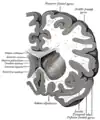

Coronal section through anterior cornua of lateral ventricles.